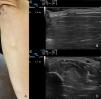

The second case is a 47-year-old woman with no relevant past medical history who visited the dermatologist with a raised asymptomatic lesion on the right forearm; the lesion had appeared 4 years earlier. The lesion was not associated with injury or other triggers. The lesion grew initially and then stabilized. Physical examination revealed a soft nodule that could be compressed on palpation (Fig. 2A). Dynamic ultrasonography was performed with the same equipment used in the previous case and showed discontinuity of the fascia of the flexor carpi ulnaris; the discontinuity was more evident on flexion and adduction of the hand (Figs. 2B and C). No treatment was required.